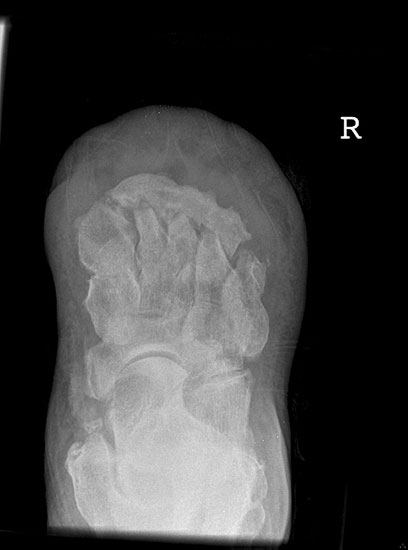

Kalkaneusteilamputationen, Kalkaneusresektion

Indikationen

• Weichteildefekte, die weder konservativ noch plastisch-chirurgisch zu decken sind,

• Lokale Osteomyelitiden mit Knochennekrose und Weichteilbeteiligung (Abb. 50).

Das Ausmaß der Knochenresektion ergibt sich aus der Defektgröße bzw. aus der Ausdehnung der Osteomyelitis 3 (Abb. 52). Eine totale Kalkanektomie ist problematisch, weil danach die Leitungsbahnen unmittelbar dem Körpergewicht ausgesetzt sind.